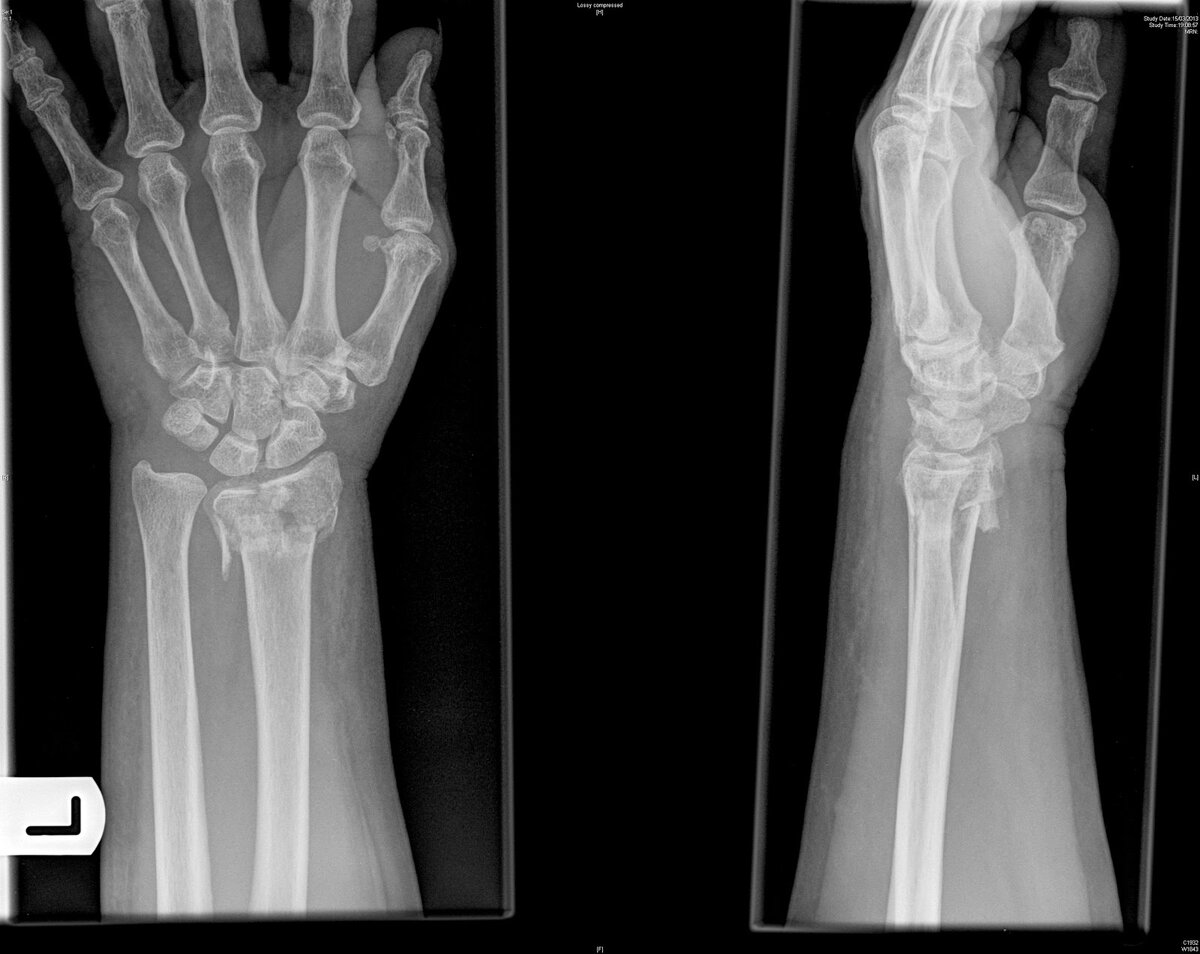

Сегодня я сломал левую лучевую кость в 3 местах.

Всем привет сегодня произошло то, что сподвигло меня нанести первый мой гипс в жизни. Я играя на футбольном поле в футбол, сломал себе левую лучевую кость аж в 3 местах.

Так как я некогда не ломал руку и не знав боли что это вообще такое, я не сильно предал этому падению значения и просто продолжил играть. Поиграв еще около 1-1.5 часа резко начала болеть рука, да не просто болеть а она оказывается немного посинела и опухла. Ну я как человек который не придавал значению данному инциденту испугался до смерти, придя в травмпункт мне сказали дружек-перелом и не обычный а в 3 местах...

После этого мне нужно 4 недели проходить в гипсе и еще 2 недели в спец повязке.